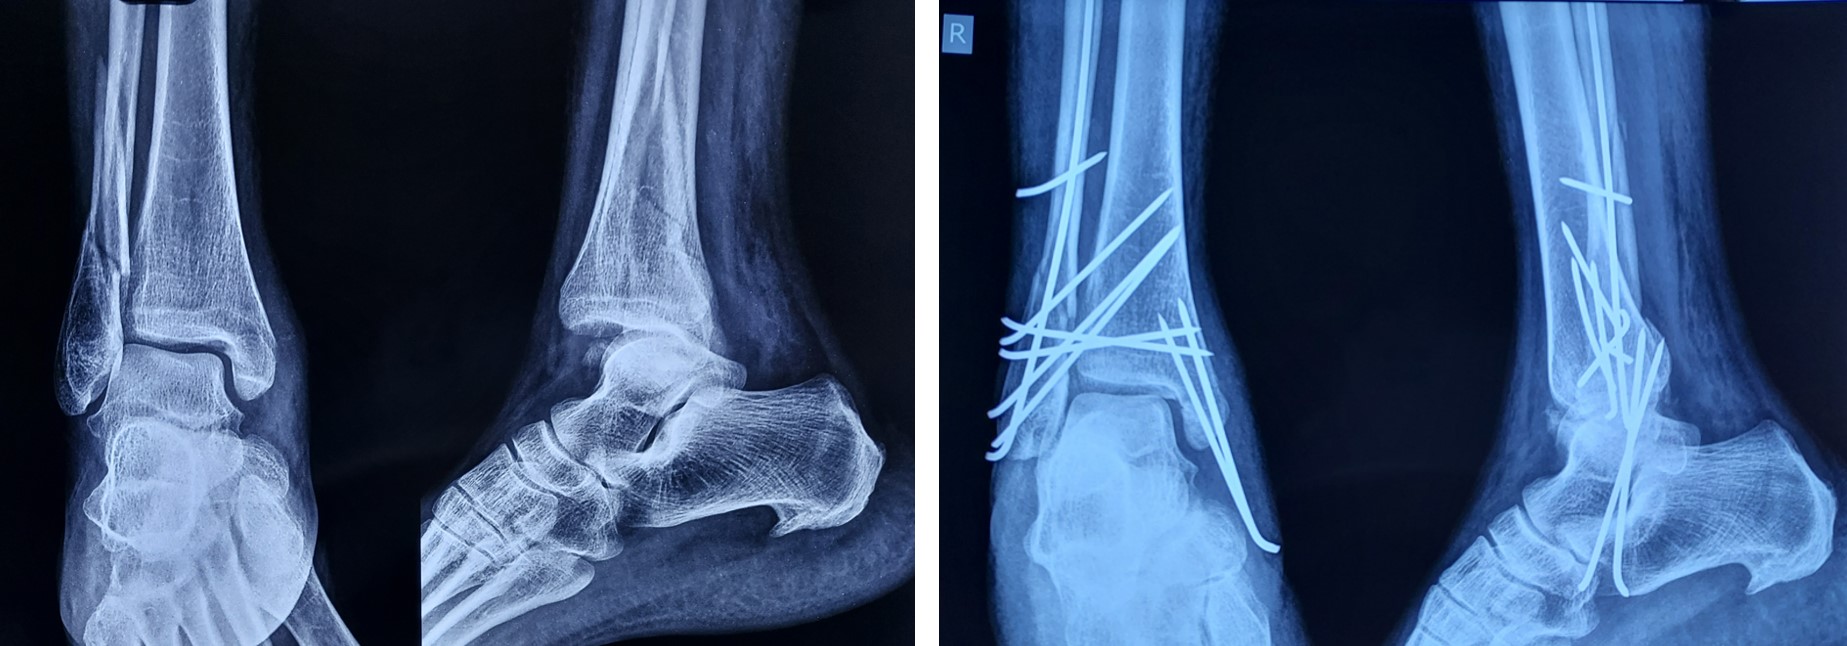

Distal 3rd Leg